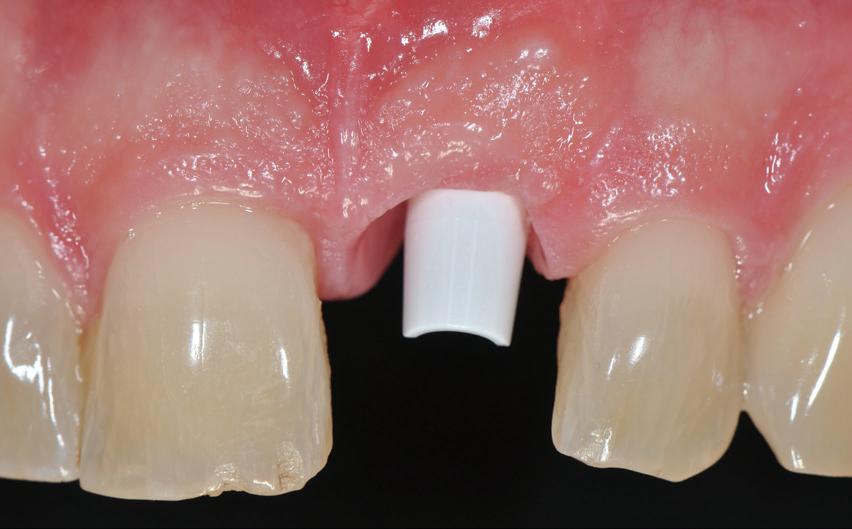

Posibilitatea ca nuanța gri să transpară prin gingie este un posibil dezavantaj al implanturilor de titan. În schimb, datorită culorii albe a dioxidului de zirconiu, această problemă estetică poate fi evitată prin

utilizarea implanturilor ceramice. Desigur, obținerea unei estetici excelente cu implanturile de titan este posibilă în mod curent. Cu toate acestea, o condiție prealabilă pentru un astfel de rezultat este prezența unei mucoase periimplantare cu o grosime de cel puțin 2 mm, care poate împiedica transparența cenușie a titanului. În lipsa acestei grosimi, mucoasa poate fi dublată de o grefă de țesut conjunctiv (recoltată de obicei din palat), necesitând însă o procedură chirurgicală adițională și, prin urmare, o povară suplimentară pentru pacient. Utilizarea bonturilor implantare integral ceramice este o soluție alternativă, dar microdeplasările bontului dur de dioxid de zirconiu pe implantul de titan mai moale pot duce la abraziune și chiar la distrugerea conexiunii implant-bont.

Totuși, ca și în cazul implanturilor de titan, în rare cazuri, și la cele ceramice poate apărea o recesie nedorită cu expunerea umărului implantar. Cu toate acestea, din punct de vedere estetic, această recesie a gingiei inflamate este posibil să fie mult mai bine tolerată de către pacienții preocupați de marginile întunecate ale implanturilor de titan (fig. 2).